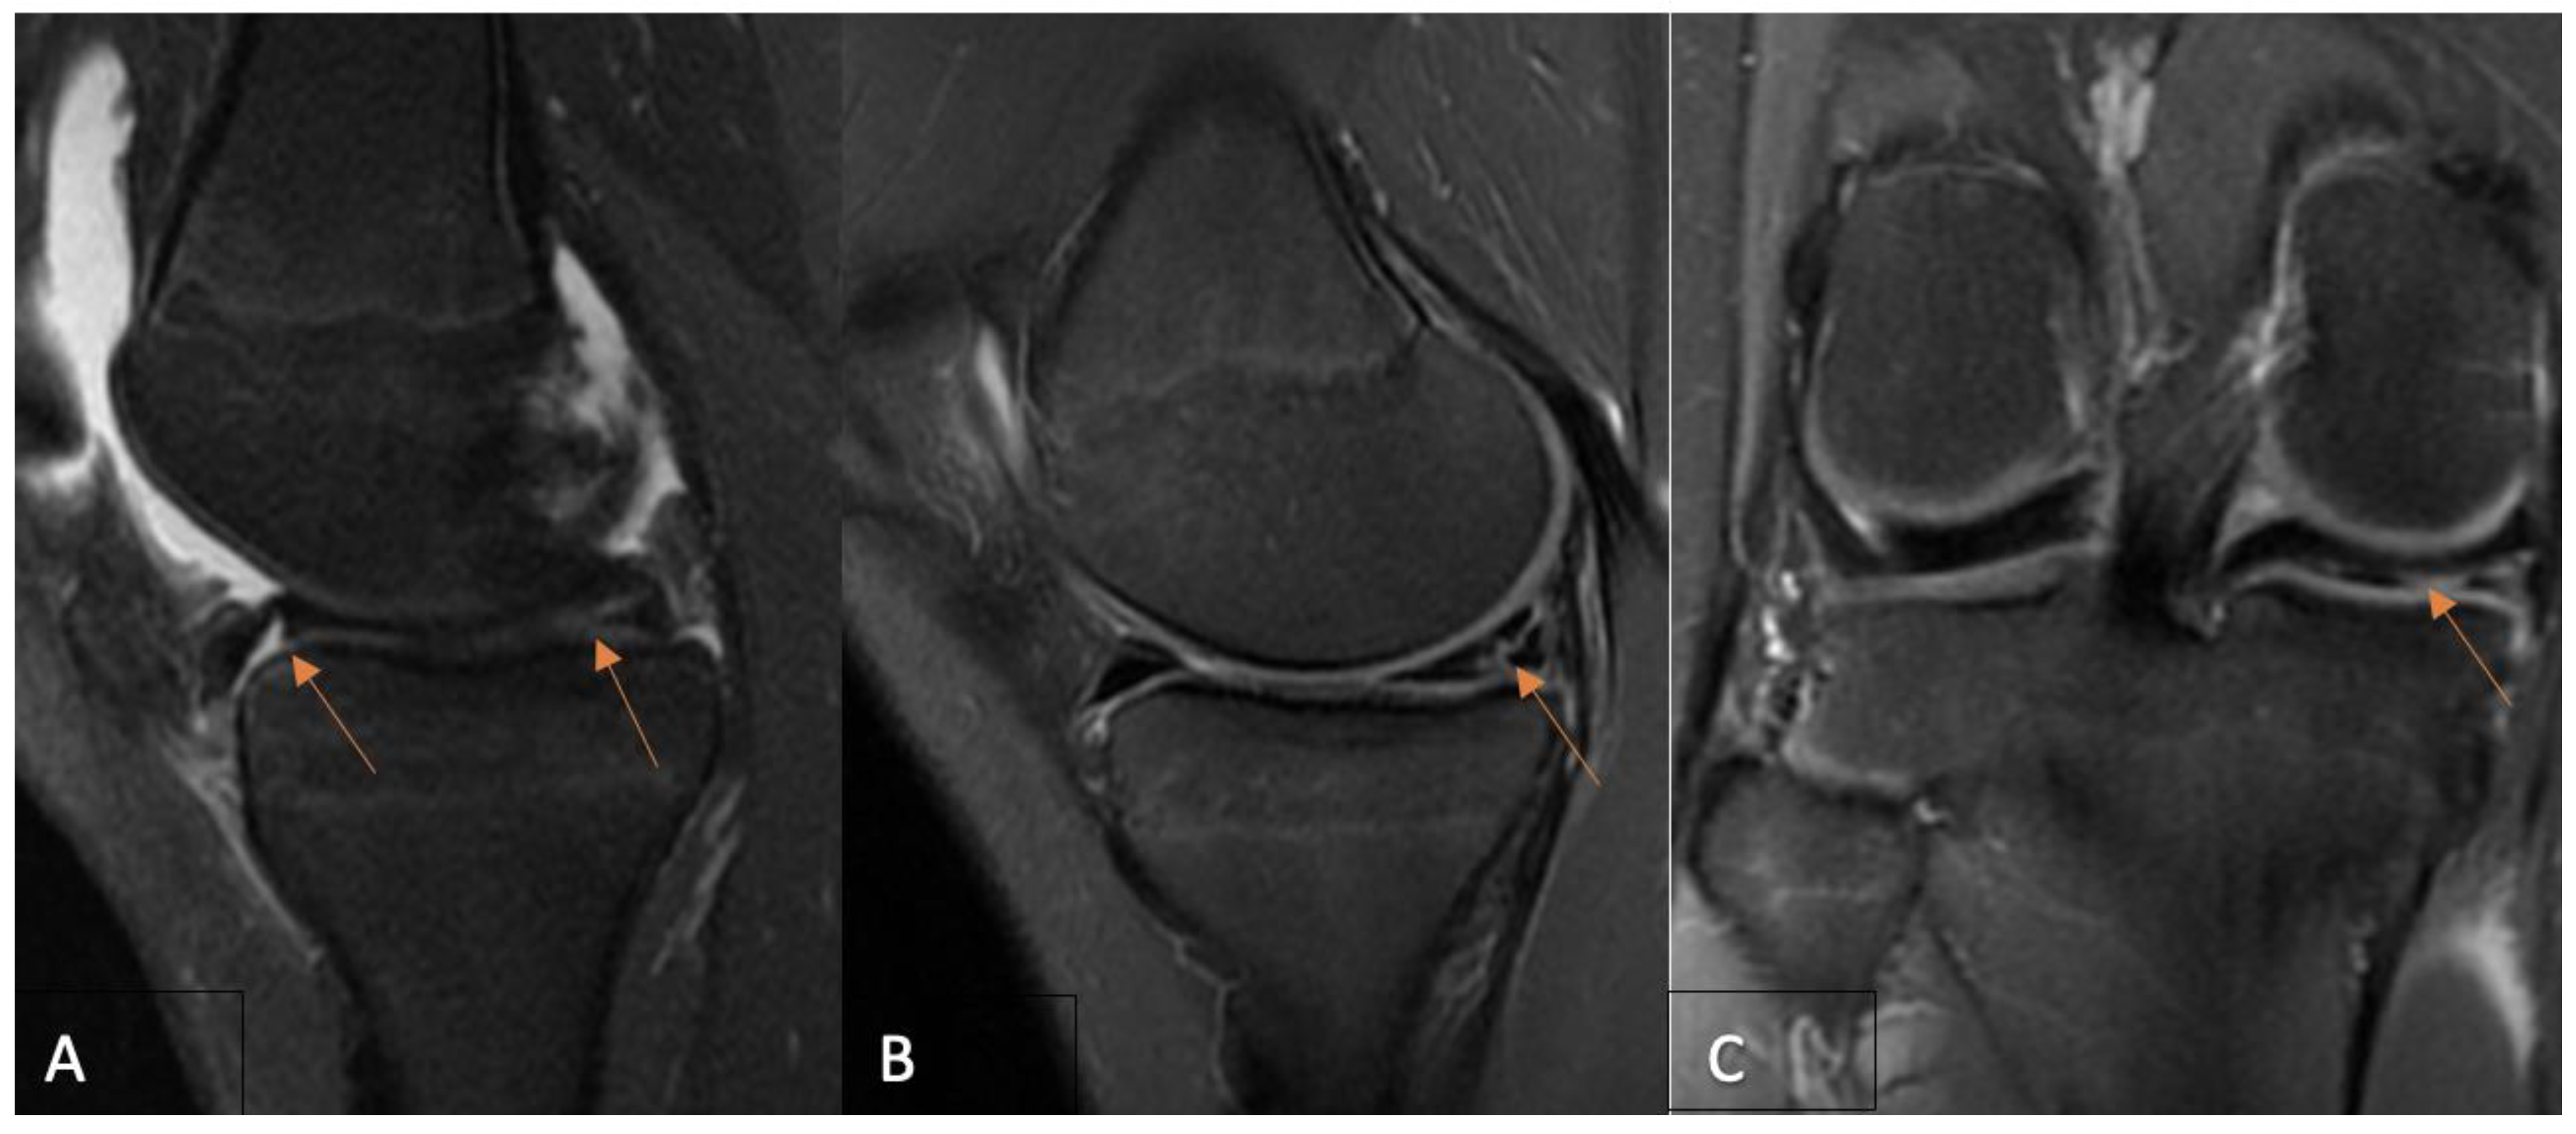

2.2. MRI Evaluation Protocol